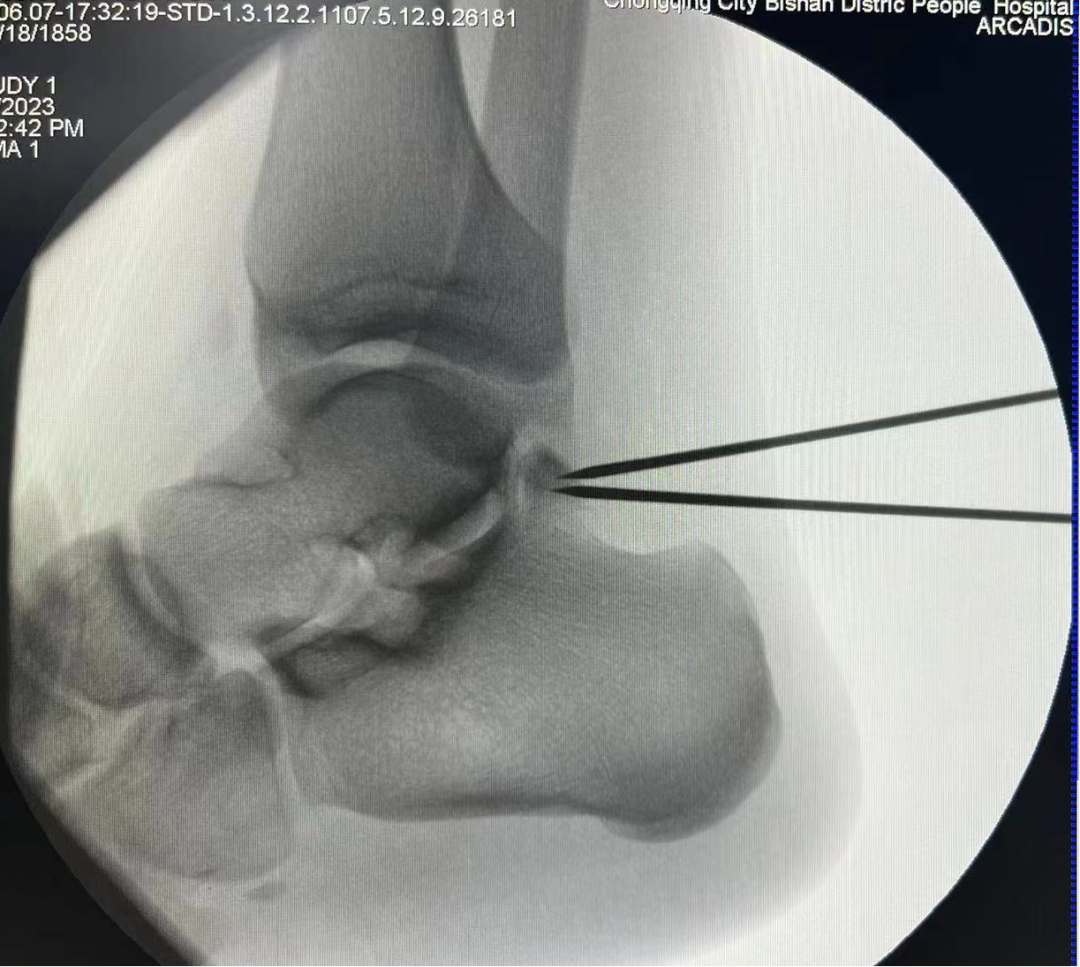

術(shù)中C臂定位病灶位置

一位19歲大學(xué)生,由于左踝長(zhǎng)期疼痛,輾轉(zhuǎn)多家醫(yī)院癥狀未緩解,嚴(yán)重影響其學(xué)習(xí)生活,經(jīng)人介紹來(lái)到我院骨科治療。骨科副主任(主持工作)彭李華博士為其進(jìn)行了全面專(zhuān)業(yè)的檢查,發(fā)現(xiàn)為三角籽骨綜合癥。完善術(shù)前檢查及準(zhǔn)備后,彭李華博士為患者行“踝關(guān)節(jié)全內(nèi)鏡下清理、松解術(shù)”。患者對(duì)手術(shù)效果滿意,已順利出院。

踝關(guān)節(jié)鏡下手術(shù)是一種微創(chuàng)治療技術(shù),其只有2-3個(gè)1cm左右的手術(shù)切口,在關(guān)節(jié)內(nèi)鏡直視下進(jìn)行手術(shù)操作,可以對(duì)踝關(guān)節(jié)進(jìn)行全方位檢查,更直觀地發(fā)現(xiàn)問(wèn)題、解決問(wèn)題。相較于傳統(tǒng)手術(shù),其具有創(chuàng)傷小、出血少、恢復(fù)快、美觀等優(yōu)點(diǎn)。